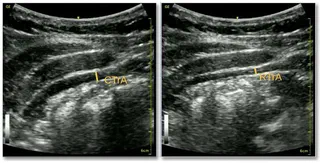

Health professionals use 2D ultrasound images to measure abdominal muscles for diagnosing and treating low back pain, but interpretation is difficult and requires specialized training. This paper presents a deep learning approach using a modified Fully Convolutional Network architecture to automate abdominal muscle thickness measurements by localizing measurement endpoints. The method achieves a Mean Absolute Error of 0.3125 on the TrA400 dataset, comparable to skilled technicians, reducing observer variability and improving clinical outcomes.